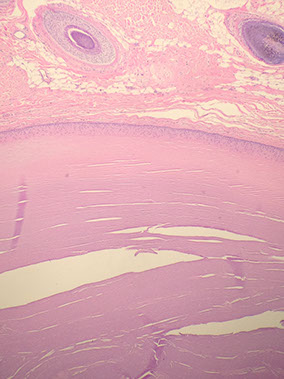

Acrochordon (skin tag)